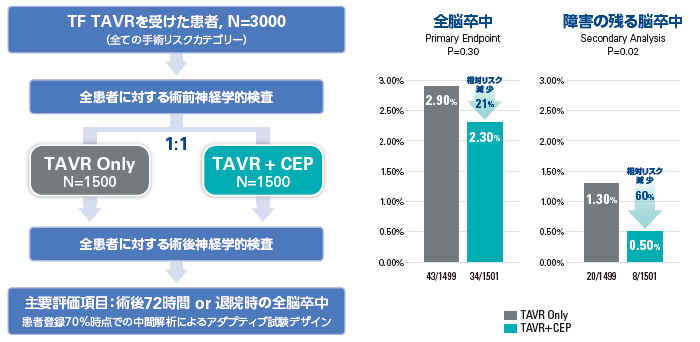

<PROTECTED TAVR 臨床試験※2>

米国、欧州及びオーストラリアの51 医療機関で大動脈弁狭窄症を有し、市販のTAVR 機器を用いた治療を受ける患者を対象に、SENTINEL の使用を評価する前向き市販後多施設共同無作為化比較対照試験を行いました。経大腿動脈アプローチで治療を受ける患者を、市販のSENTINELを使用する被験群又はSENTINEL を使用しない対照群のいずれかに1:1 の割合で無作為に割り付け、計3,000 例が登録されました。PROTECTED TAVR 臨床試験では、本製品を使用してTAVIの治療を受けた患者さんは、使用せずにTAVIの治療を受けた患者さんと比較して相対的に、全脳卒中のリスクが21%減少、障害の残る脳卒中のリスクが60%減少しました※3。

全コホート(3,000 例)における主要評価項目に対する優越性検定において、TAVR 手技後72 時間又は退院時(いずれか早い時点)までの全脳卒中(障害を伴うもの又は伴わないもの、出血性、虚血性又は原因不明)とした主要評価項目は、主要解析対象集団であるIntent-to-treat(ITT)解析対象集団でSENTINEL群2.3%、対照群2.9%であり(p=0.2960)、主要評価項目は満たされませんでした。特に、障害を伴う脳卒中はSENTINEL群(0.5%)の方が対照群(1.3%)よりも有意に少ない結果(p=0.0225)となりました。

図1 試験デザイン 図2 試験結果